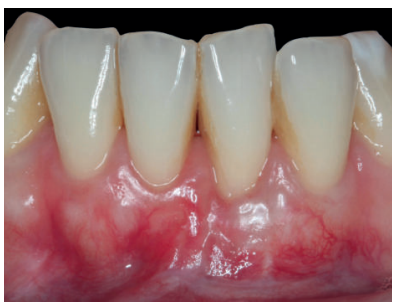

El examen clínico periodontal reveló la presencia de recesión gingival de 5 mm en el diente 31 con una profundidad de sondaje vestibular de 2 mm (perdida de inserción clínica de 7 mm). Presentaba inflamación gingival, además de un frenillo labial inferior insertado en el margen apical de la recesión gingival. El tejido queratinizado faltaba por completo a nivel del diente con recesión (Figura 1). Debido a que el defecto gingival se extendía más allá de la línea mucogingival, así como a la presencia de malposición dentaria, la recesión se categorizó como clase III de Miller6 y RT2 de Cairo7 .